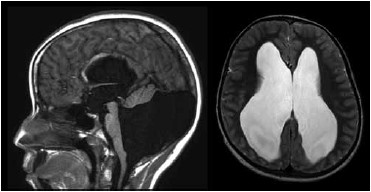

Paciente do sexo feminino, 8 anos, há um mês sofre de cefaleia holocraniana diária associada a vômitos, com melhora parcial com analgésicos. Ao exame, apresenta papiledema. Realizou a ressonância de crânio a seguir.

O diagnóstico é hidrocefalia secundária